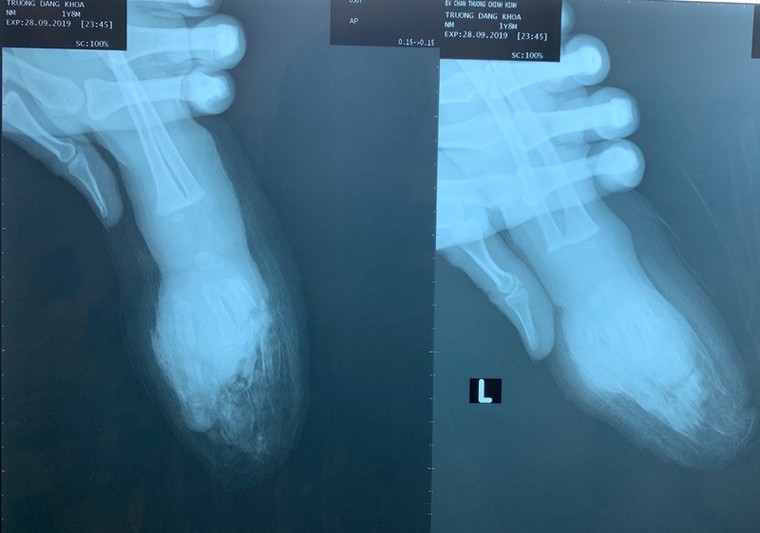

Giữa bàn tay trái cùng bốn ngón tay bé K. bị đứt lìa - Ảnh: BV cung cấp)

Trao đổi với báo Tiền Phong, BS Võ Hoà Khánh cho biết, BV tiếp nhận bệnh nhi trong tình trạng đứt lìa ngang giữa bàn tay trái, đứt lìa đốt xa ngón trỏ tay phải,  vết thương bầm dập nhiều.

Sau khi tiếp nhận bệnh nhân, các BS đã tiến hành cắt rửa lọc vết thương, nối vi phẫu cứu bàn tay trái và khâu mỏm cụt bàn tay phải cho bé. Ca mổ diễn ra trong 8 tiếng và đã thành công.

Hiện sức khoẻ bệnh nhi khá ổn định, không có dấu hiệu nhiễm trùng, bàn tay trái tưới máu tốt. Tuy nhiên, theo BS Khánh, bệnh nhi vẫn đang tiếp tục được theo dõi vì nguy cơ nhiễm trùng (do sên xe dơ và có nhiều dầu nhớt), nguy cơ tắc mạch máu ( do mạch máu bé 1 tuổi rất nhỏ) là rất cao.